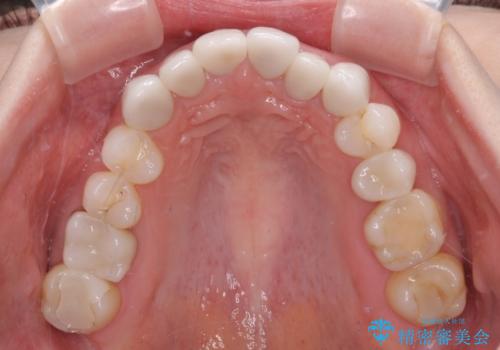

- 上下前歯のデコボコと奥歯の欠損を気にして来院された患者様です。

右下の欠損分は奥歯が倒れ込んでスペースがなくなっていたため、矯正治療により本来の位置に歯を移動させ、オールセラミックブリッジによる欠損補綴治療を行うこととしました。

全顎的にセラミッククラウンが多く装着されているため、インビザラインによる矯正治療を行うこととしました。

右下は移動量が多いため、十分な移動が達成されない場合はワイヤー装置を使用する予定としておりましたが、しっかりとマウスピースを装着してくださったため、前歯とともに十分に歯を動かすことができました。